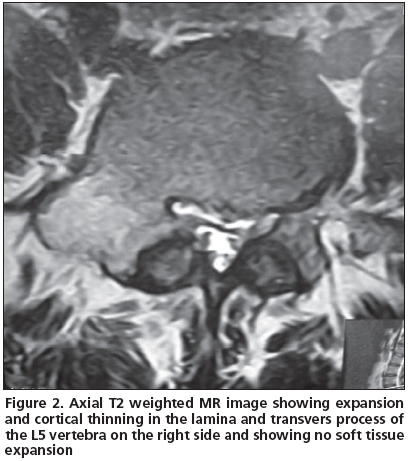

A 21 year-old male patient admitted to our clinic with low back pain persistent to medication for the last 3 years. He was first referred to physical medicine and rehabilitation department and then to a neurosurgery department after several visits because of persistent pain. He had no history of trauma. His pain was not aggravated by coughing, standing or sitting; and the pain was not relieved by salicylates or NSAIDs. Whole blood count (CBC), erythrocyte sedimentation rate (ESR) and rheumatoid factor (RF) were found within normal limits. Physical examinations were found normal except the tenderness extending from T12 to L5 associated with paravertebral muscle spasm. His lumbosacral CT was taken and then a tumoral mass was noticed enlarging transverse process and right lamina of L5 vertebrae with probable diagnosis of osteoblastoma or osteoid osteoma. The mass had a lytic nature with well defined osteosclerotic boundaries and facet joints were normal (Figure 1). An MRI was taken to evaluate the soft tissue expansion which showed no affection (Figure 2). A CT-guided biopsy resulted with unsatisfactory sample gathering. Then he has taken to the operation theatre and curettage and frozen section was performed since the probable diagnosis was osteoblastoma. After confirmation of benign tumoral process, the cavity was filled with allograft. The histopathological examination confirmed the diagnosis of osteoblastoma. Following surgery, the patient was asymptomatic; there was no neurological dysfunction and no residual pain or discomfort. No recurrence has been observed for four years.